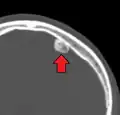

Osteoma of the frontal sinus seen on x-ray -

Osteoma of the frontal sinus on CT -